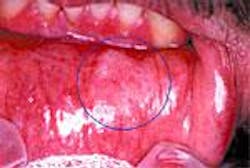

Oral Cancer Lesions

Photos reprinted by permission of CDx Laboratories, Inc.